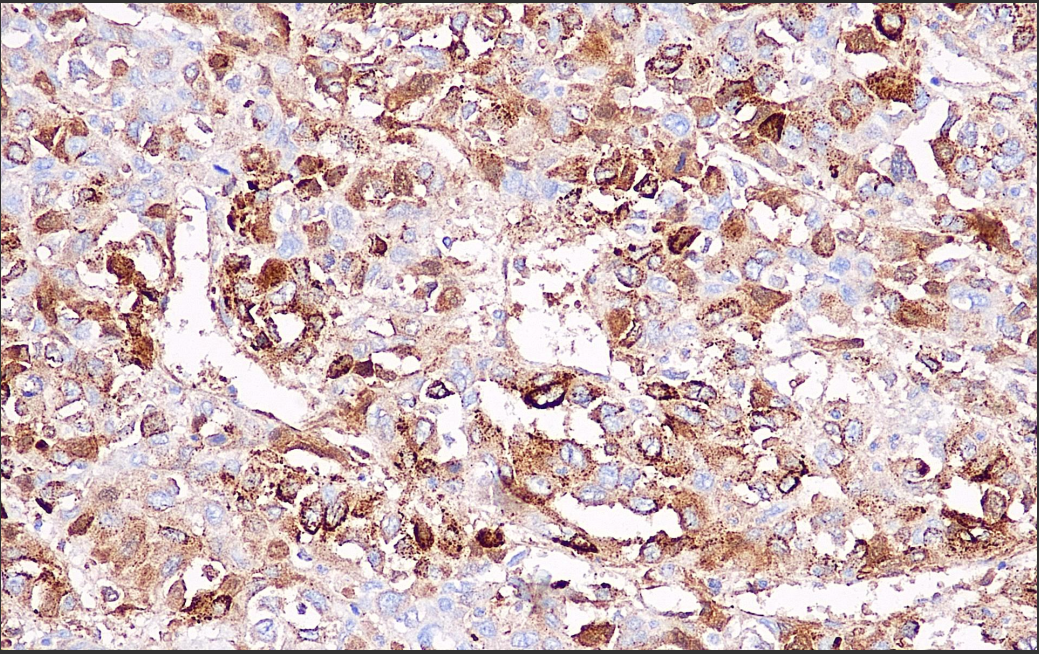

Positive control: Liver cancer

AFP is a glycoprotein synthesized by embryonic yolk sac cells, embryonic hepatocytes and fetal intestinal cells. It is highly expressed in the liver of the fetus and is not expressed in the normal adult liver. However, hepatocellular carcinoma, endodermal sinusoidal tumors and certain germ cell tumors such as yolk sac tumors show positive expression of this antibody. Therefore, AFP is commonly used in the study of neoplastic and non-neoplastic liver diseases, yolk sac tumors and other germ cell tumors.

Alpha-1-Fetoprotein Antibody Reagent binds specifically to the Alpha-1-Fetoprotein molecular antigen. Immunohistochemistry kits containing Alpha-1-Fetoprotein Antibody Reagent are indicated for the precise diagnosis of neoplastic and non-neoplastic liver diseases, yolk sac tumors and other germ cell tumors.